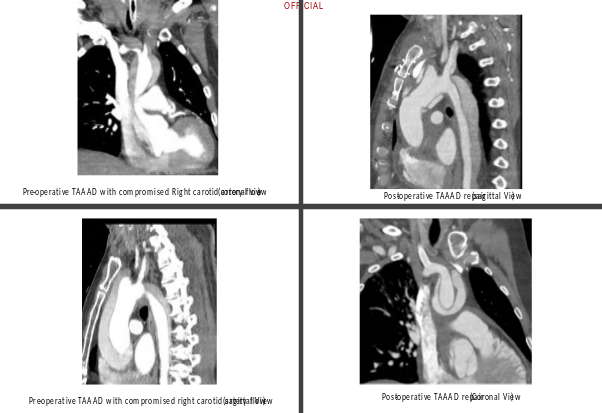

A sixty-four-year-old man presented to the emergency department with a history of syncope followed by tonic-clonic seizures and dense left hemiplegia, without chest or back pain. Because of low GCS, urgent intubation was required. Five years earlier, the patient had undergone an abdominal aortic aneurysm repair, and he had been under annual surveillance for a 45 mm ascending aortic aneurysm. On a head and neck CT with a brain perfusion scan, a significant right MCA area and right frontal lobe infarct without hemorrhagic changes were visible along with evidence of ATAAD affecting the aortic arch and its branches (Figure 2). On the gated CT aortogram, an extensive ATAAD involving arch vessels was visible from the ascending aorta to the abdominal aorta (Figure 1). Both true and false lumens supplied blood to the brachiocephalic artery, and the right common carotid artery's flow was compromised.

Figure 1

The multidisciplinary team's immediate suggestions included percutaneous fenestration and transluminal angioplasty of the right common carotid artery, followed by an MR perfusion scan to reassess cerebral circulation. Through the right common femoral artery, a successful percutaneous fenestration procedure into the right common carotid artery was carried out, and a stent was successfully deployed (Figure 3).

The patient experienced hemodynamic instability during MR imaging, necessitating an urgent pericardiocentesis, followed by prompt ATAAD central aortic repair with right femoro-femoral cardiopulmonary bypass. An antegrade cerebral perfusion via the brachiocephalic artery and hypothermic circulatory arrest at 24°C were used during the surgical procedure. By using the open distal approach, a supracoronary ascending aorta replacement and aortic valve resuspension procedure were performed. Recovery after surgery was difficult because of the patient's prolonged ventilation and acute kidney injury, which resolved within seven days. The patient was discharged home from stroke rehabilitation on postoperative day eighteen after full recovery from left hemiplegia.